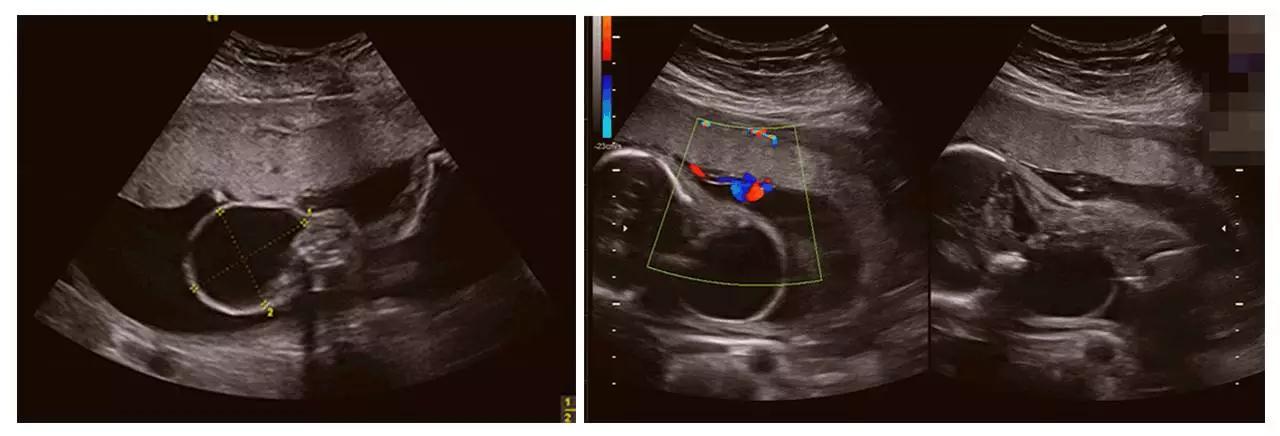

成功筛查胎儿畸形的案例(部分)

(左心发育不良)

(胸腹腔积液、全身水肿)

(颈后水囊瘤)

以上案例更多的是警示我们超声影像(四维彩超)检查的重要性。我们希望每个宝宝都能健康成长。